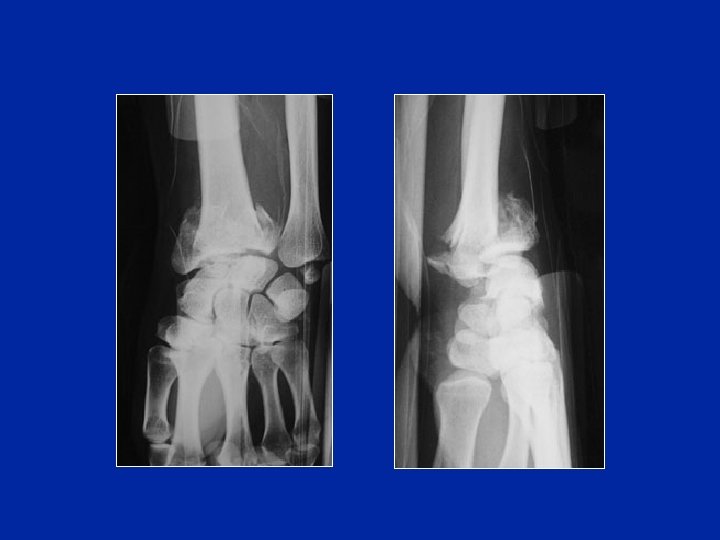

Fracturas Articulares

Clasificación de las fracturas de la extremidad inferior del radio